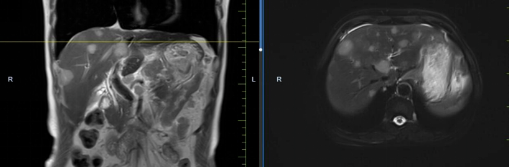

患者馬某某,男,60歲,因腹部不適行胃鏡及腹部CT,提示胃癌、多發(fā)淋巴結(jié)轉(zhuǎn)移、肝轉(zhuǎn)移,胃部病灶大小約11*6cm,淋巴結(jié)最大病灶約6*3cm,肝臟病灶最大約8.8*7cm。經(jīng)6周期化療+免疫,聯(lián)合中醫(yī)中藥后,病灶明顯縮小,進(jìn)入維持治療階段,身體狀況與常人無異。

治療前